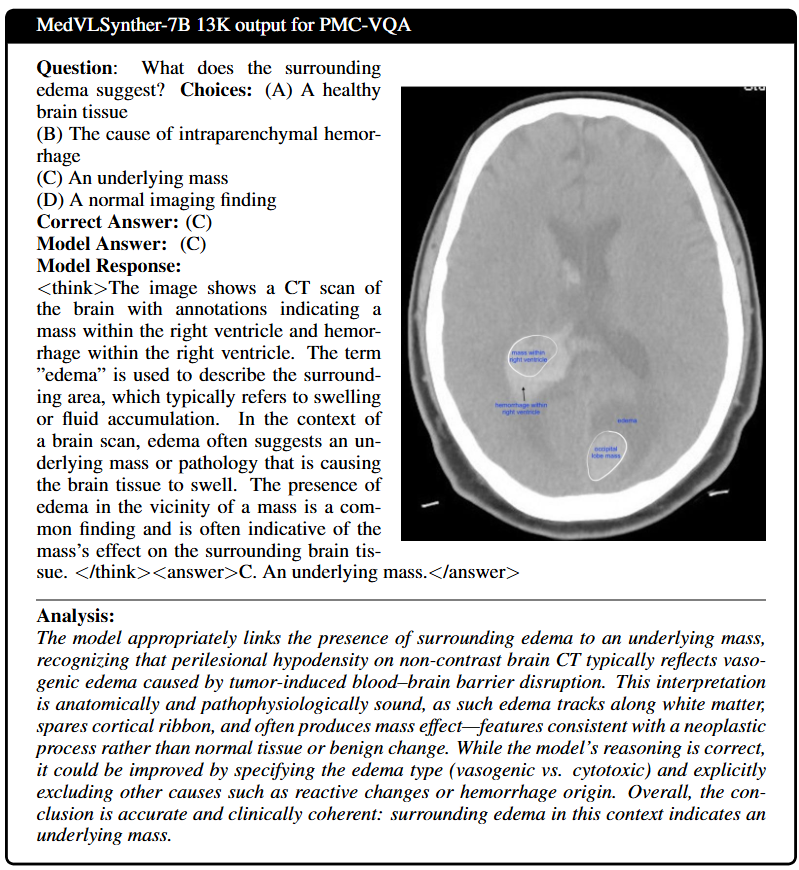

Qualitative Results

Two auto-scrolling rows: 3B cases (top) and 7B cases (bottom). Click any panel to open full-size.

3B Cases

7B Cases